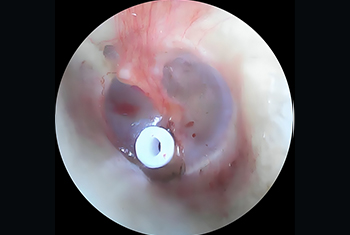

Comprehensive care for ear infections and hearing loss, including Tympanoplasty, Mastoidectomy, Ossiculoplasty and Stapedotomy/Stapedectomy for improved hearing outcomes.